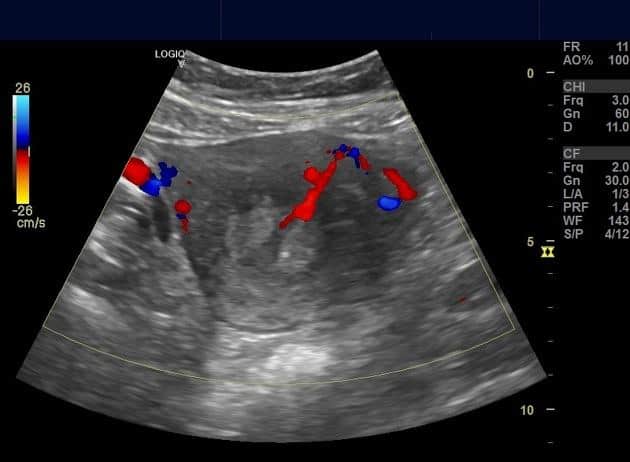

Polyp nội mạc tử cung

» Thông tin: Nữ giới – 40 tuổi.

» Lâm sàng: Rong kinh.